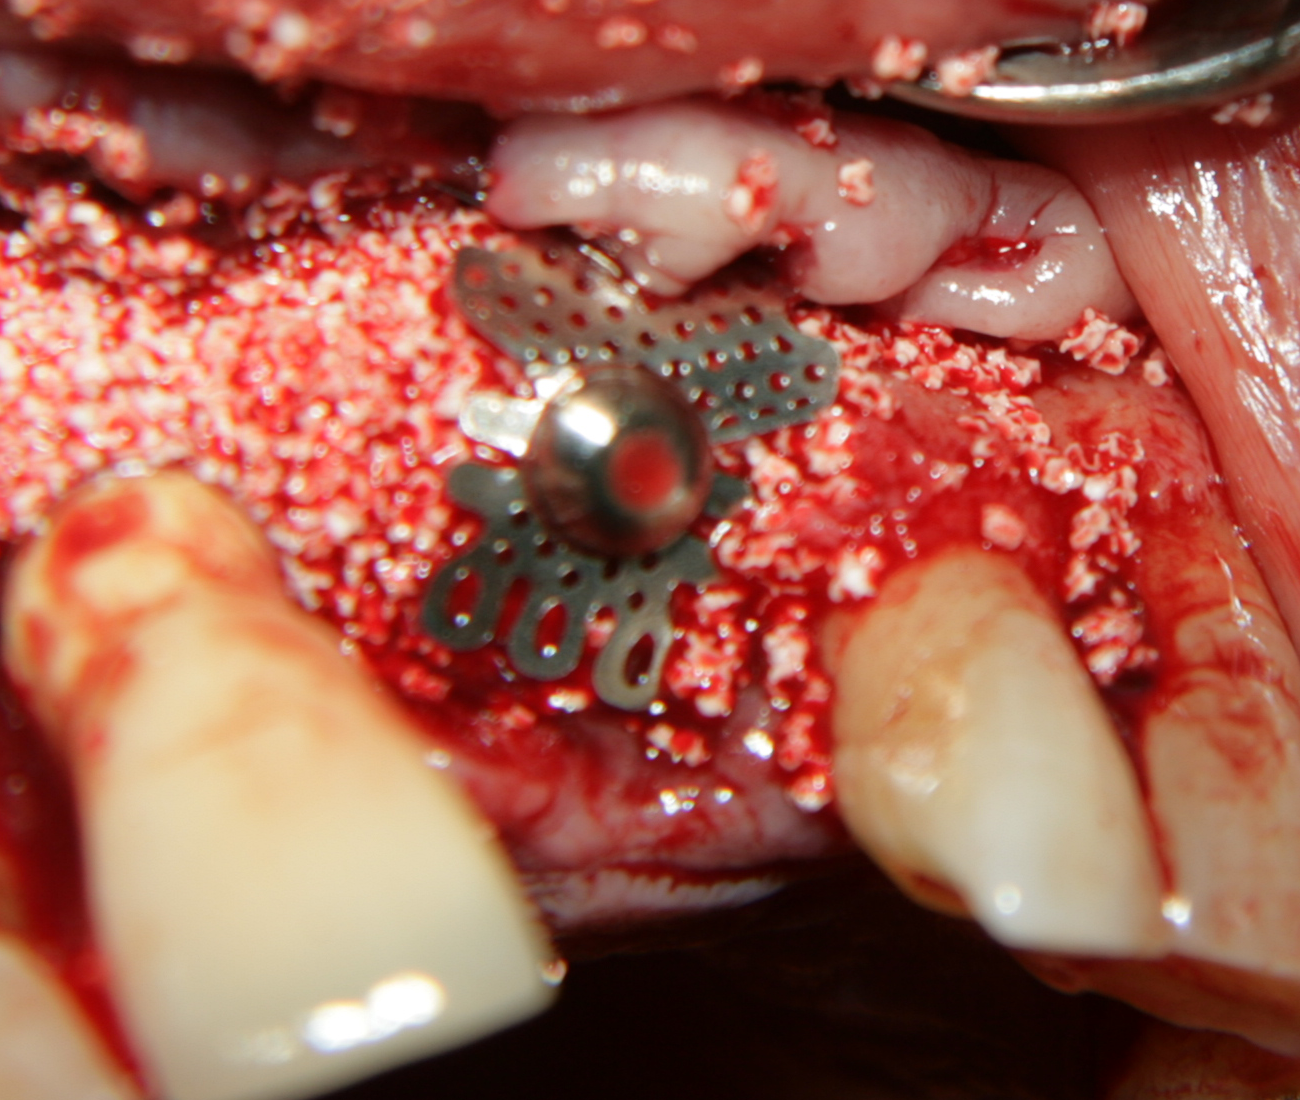

Титановите мембрани са твърди, ригидни приспособления, които се поставят в участъци с необходимост от увеличаване на костния обем - най-вече в областта на имплантологията, но също при радикуларни кисти и много рядко след екстракция на ретинирани мъдреци, при дефкетни фрактури, пострезекционни дефекти на челюстите, тежки остеомиелити и специфични възпаления на костта. Идеята на титановата мембрана е да предпази меките тъкани от колапс, поне за известен период от време, през който период под мембраната да започне костообразуване. През първите шест - осем месеца титановата мембрана оказва своя ефект, след което вече е безсмислено да остава в устата на пациента.

При операции с цел изграждане на допълнителн костна тъкан (костна пластика) винаги е добре да се перфорира кортикалната пластинка на костта. През тези перфорации излизат костни клетки, които постепенно прорастват в котозаместващия материал и синтезират нова костна тъкан. Перфорациите могат да се извършат с кръгло борче или с АСМ - фрезата на Neobiotech - Южна Корея.

Tent screw - винтове за

фиксиране на титановата мрежа

Около винтовете се поставя костозаместител, добре е да се размеси с

автогенна кост

Титанова мембрана